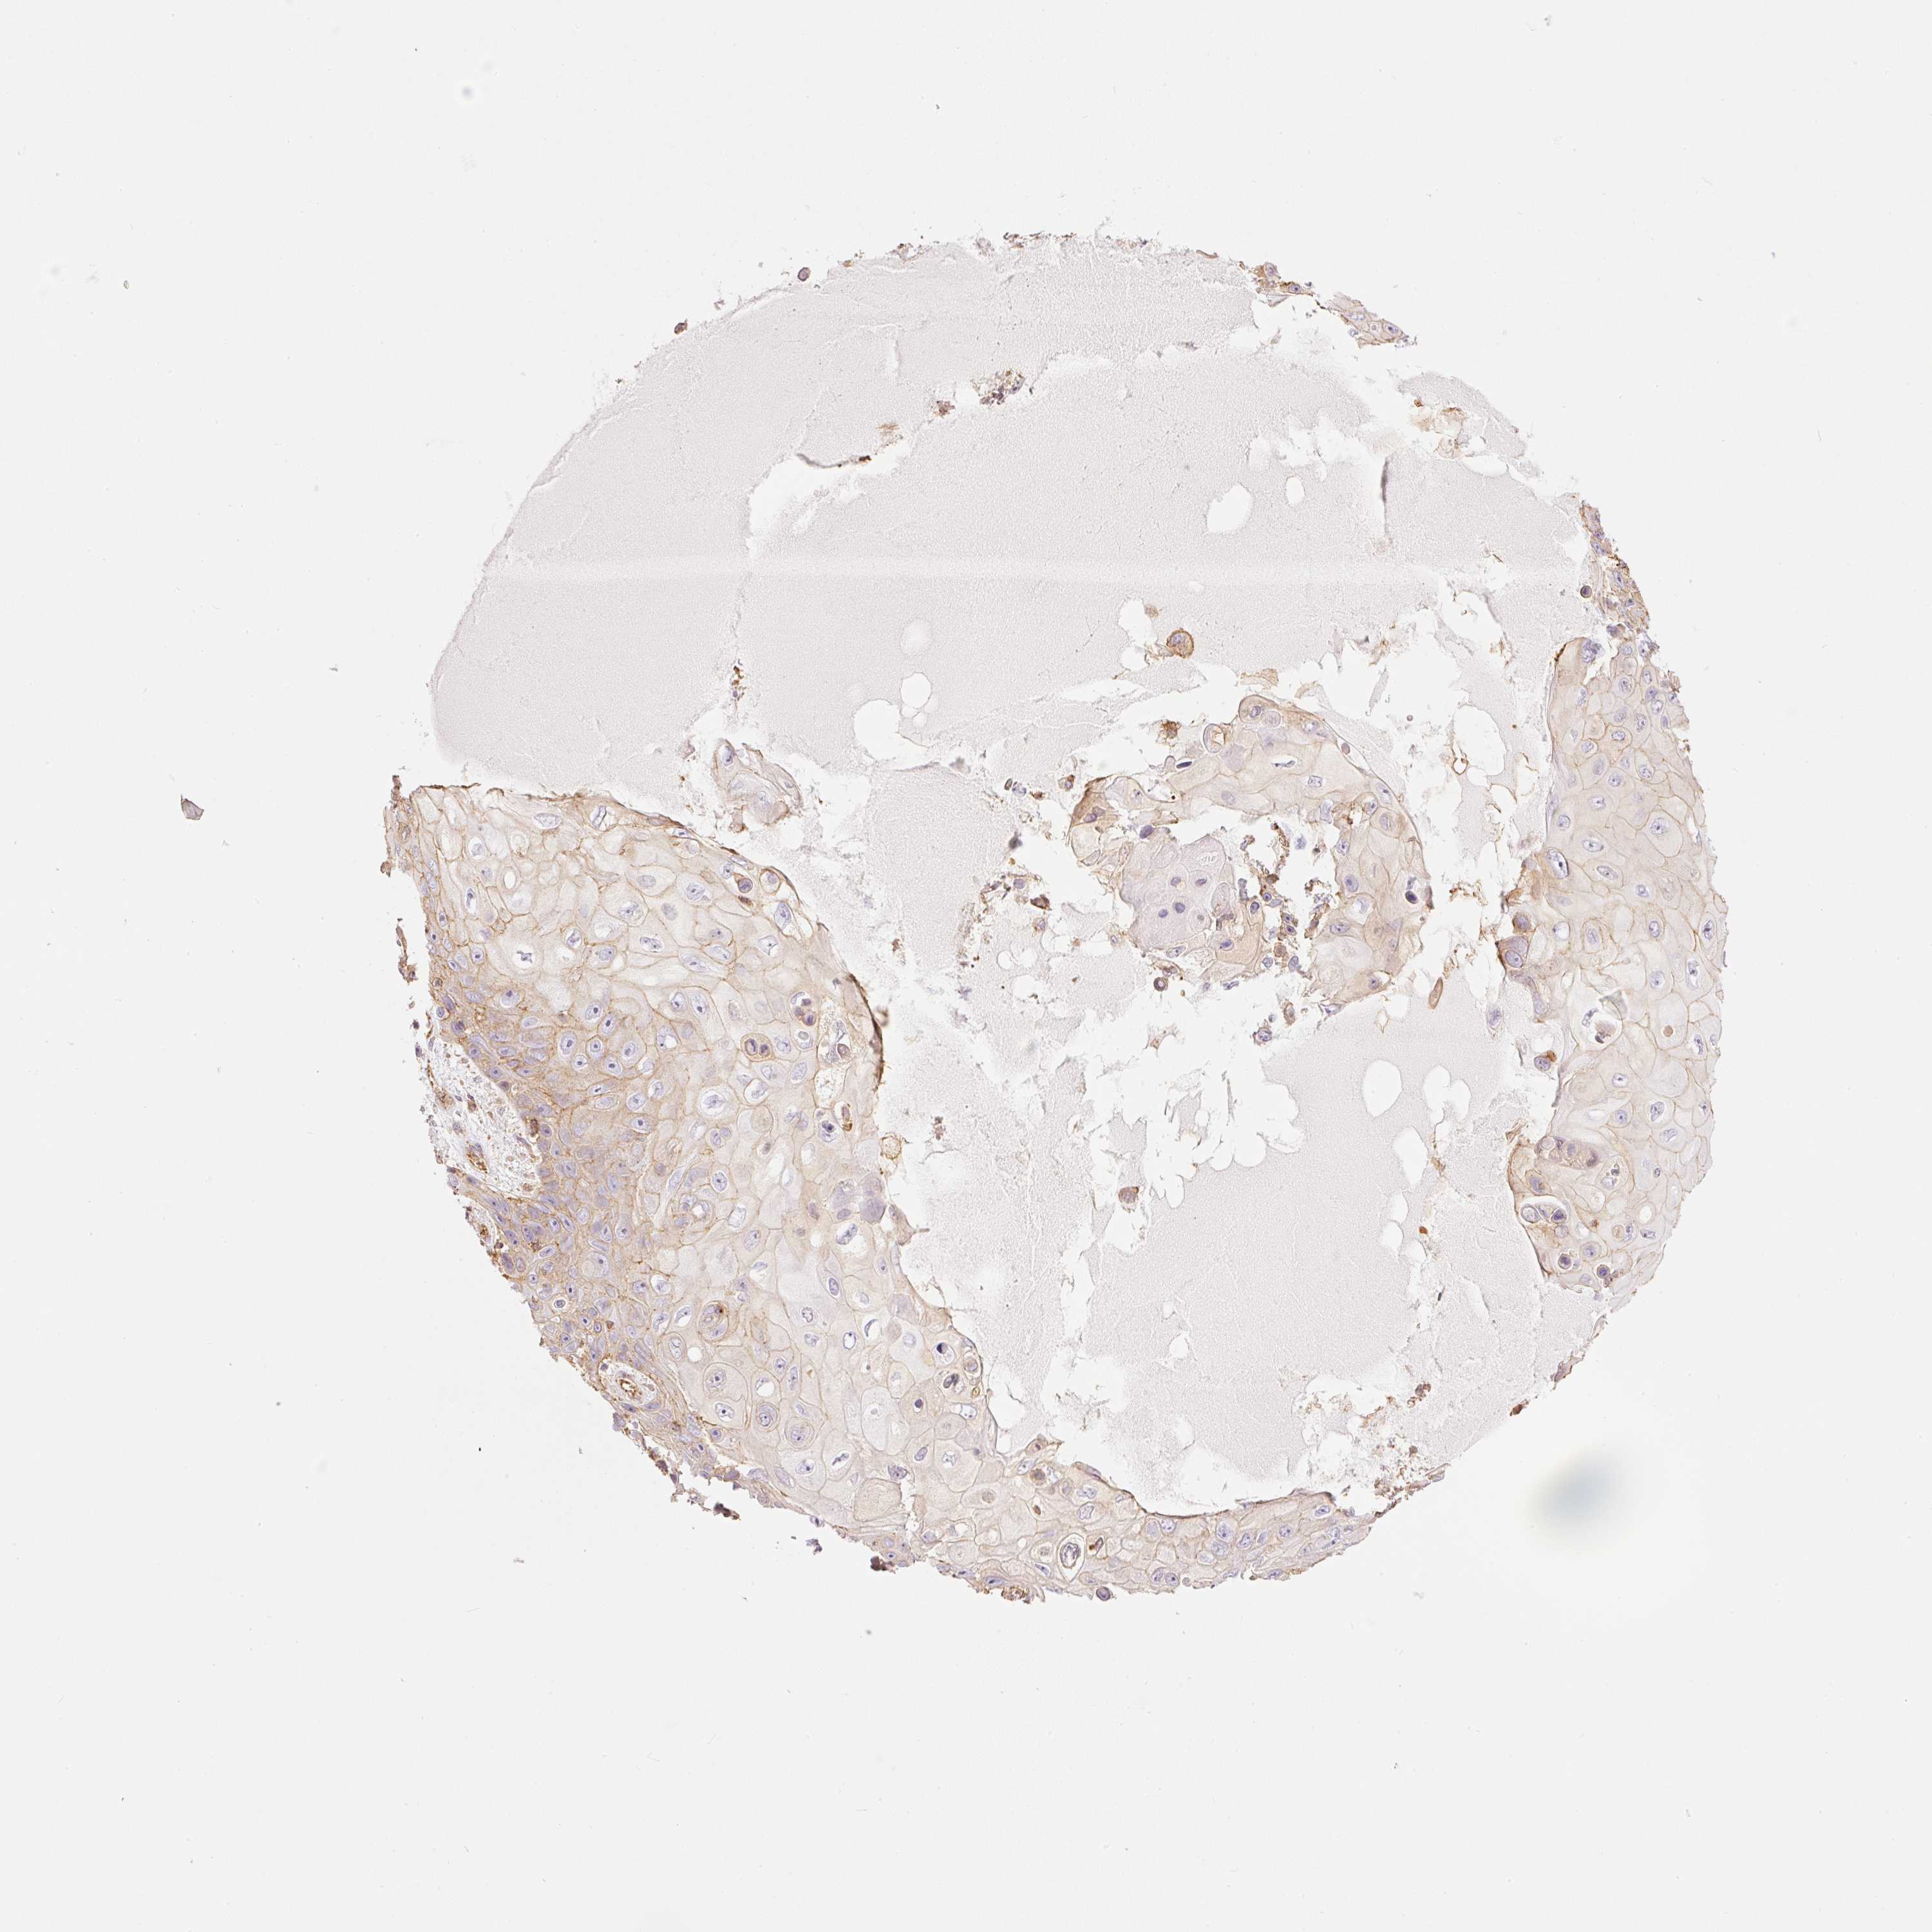

SKIN CANCER - Protein expressioni

A mouse-over function shows sample information and annotation data. Click on an image to view it in a full screen mode. Samples can be filtered based on level of antibody staining by selecting one or several of the following categories: high, medium, low and not detected. The assay and annotation is described here.

Each image is clickable and will lead to virtual microscopy that enables deeper exploration of all samples and also displays staining intensity scores, fraction scores and subcellular localization as well as patient and tissue information for each sample.

Antibody HPA048630

Antibody HPA061142

Antibody CAB004026

Staining

High

Medium

Low

Not detected

Intensity

Strong

Moderate

Weak

Negative

Quantity

>75%

75%-25%

<25%

None

Location

Nuclear

Cytoplasmic/membranous

Cytoplasmic/membranous,nuclear

Basal cell carcinoma

Squamous cell carcinoma, NOS